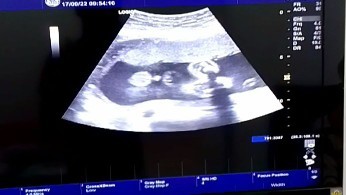

ผู้ชายค่ะ สมใจป๊าป๊าเขาเลย

หมอบอกชาย ทำไมเล็กจัง

บ้านนี้โชว์เต็มที่